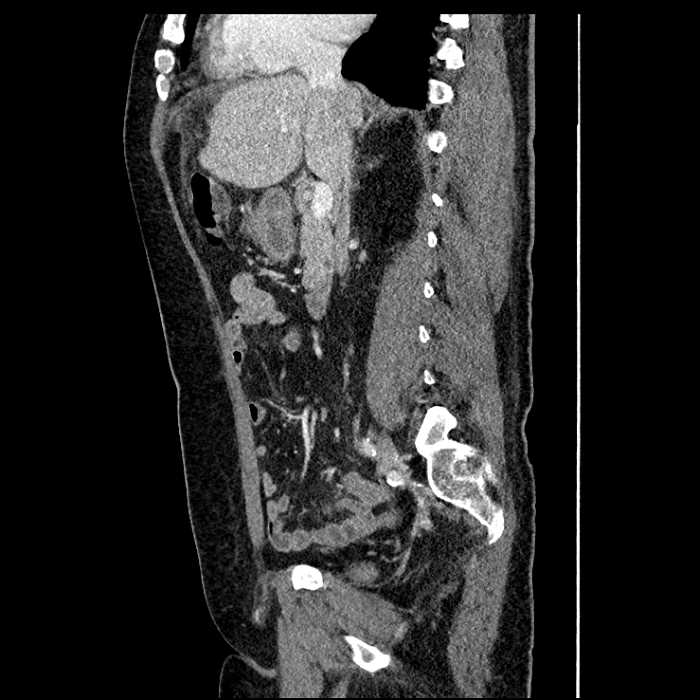

• Mild mural thickening of a segment of the sigmoid colon with adjacent fat stranding and a 1.5 cm fluid and gas collection along the tip of an inflamed diverticulum

• Loss of the normal fat plane between this collection and adjacent loops of small bowel, which demonstrate mural thickening

Acute sigmoid diverticulitis complicated by a small contained perforation and a large abscess in the right hepatic lobe. Additional small subcapsular abscesses along the anterior margin of the left hepatic lobe.

Additionally, loss of the normal fat plane between the peridiverticular collection and adjacent thickened loops of small bowel raises the potential for an enterocolonic fistula.

Hepatic abscess showing the double target sign with low density internally surrounded by a thin inner enhancing rim (red arrow) and ill-defined outer low density rim (yellow arrow). Blue arrow indicates an internal septation. Red arrows: additional smaller subcapsular abscesses. Red arrow: focal contained perforation associated with diverticulitis.